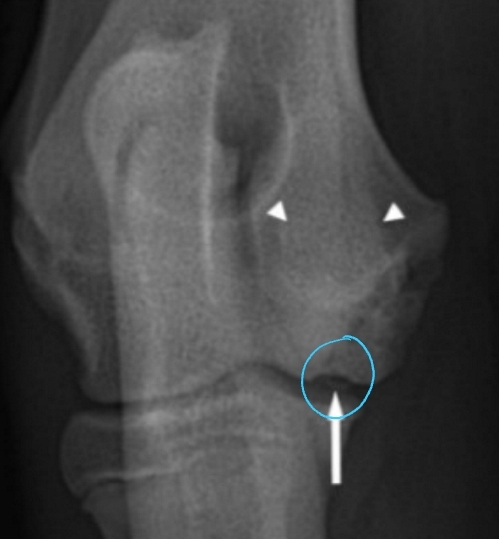

Cranial Cruciate Ligament Disease Diagnosis

PE: Crouched hindlimbs, external rotation of affected limb, Failed “sit test”

Acute clinical presentation

Meniscal Click: Torn meniscus pops due to shear with range of motion

Radiographs: Joint effusion, Medial periarticular fibrosis(medial buttress), Osteophytosis, Cranial drawer placement, OA